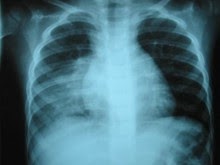

La reducción de los niveles de vitamina D vinculados a pneumonia Un breve informe publicado en línea el 17 de abril de 2013, de la Revista de Epidemiología y Salud Comunitaria revela un efecto protector de los niveles más altos de vitamina D con el riesgo de desarrollar neumonía.

| Neumonia. |